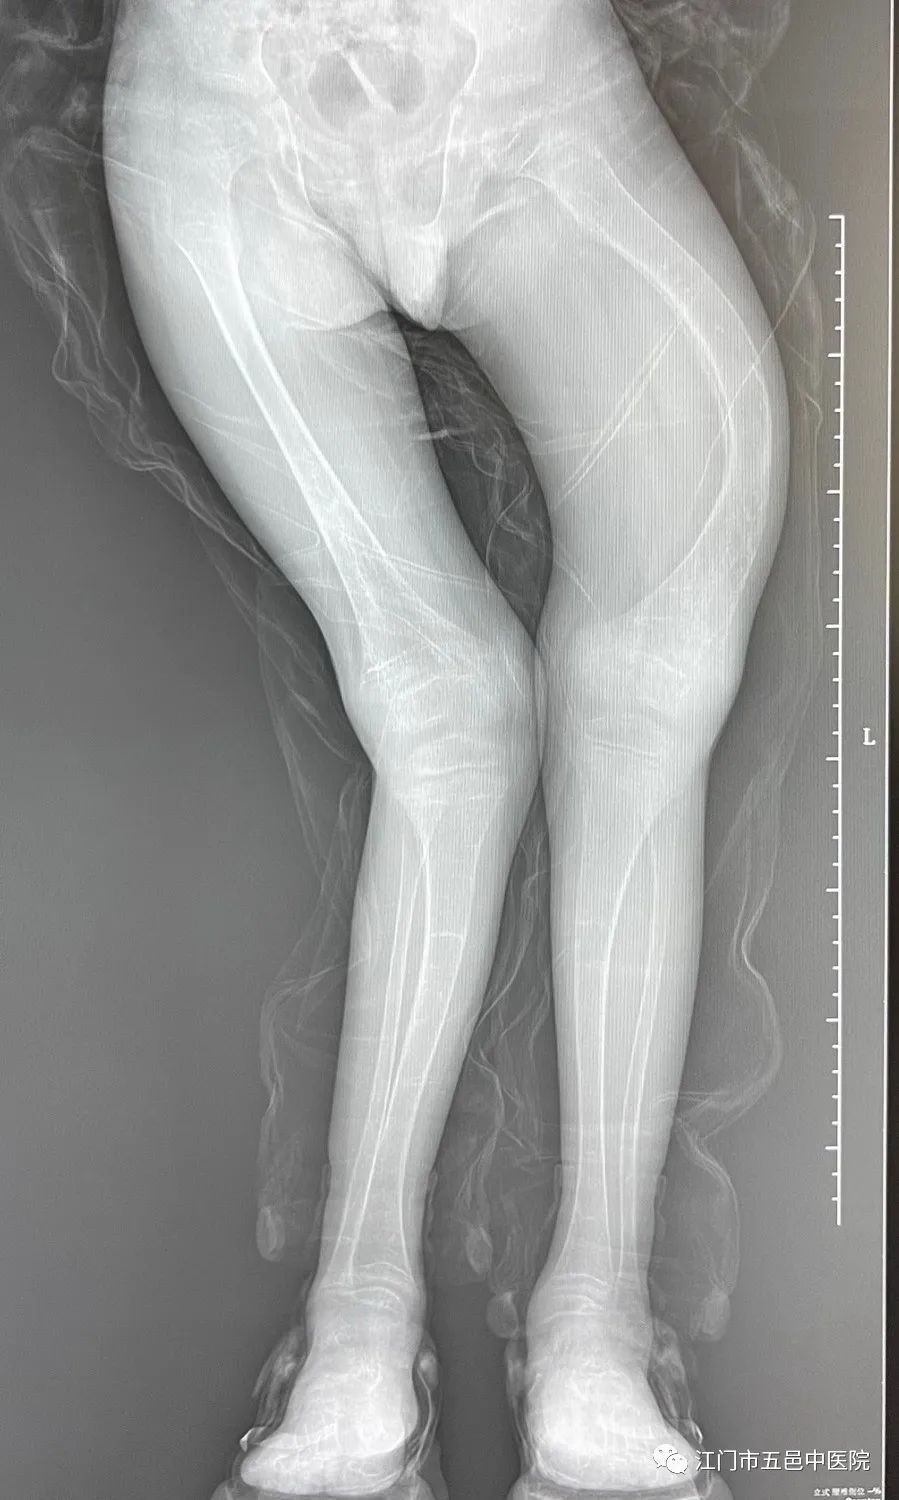

▲术前站立位双下肢全长DR

11岁的小豪身高仅约1.02米,双膝外翻畸形严重,左股骨亦存在严重的弯曲畸形。结合患儿身体情况,廖医生建议分两次完成手术矫形。